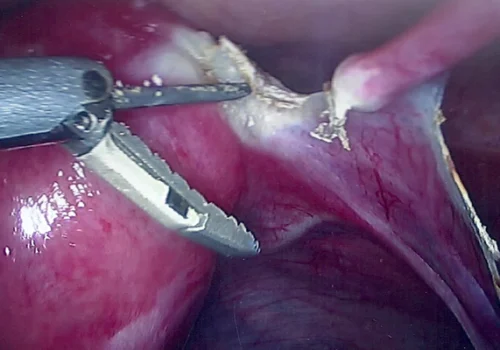

Florid Adenomyosis - Total Laparoscopic Hysterectomy

Procedure

She requested a hysterectomy – and subsequently underwent a Total Laparoscopic Hysterectomy with removal of both tubes and ovaries.